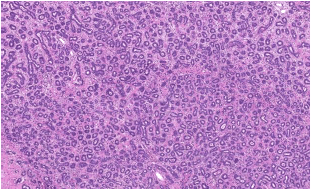

A presença desta pequena coleção de células ilustrada na imagem abaixo tem relação com . Assinale a alternativa que preencha corretamente a lacuna.